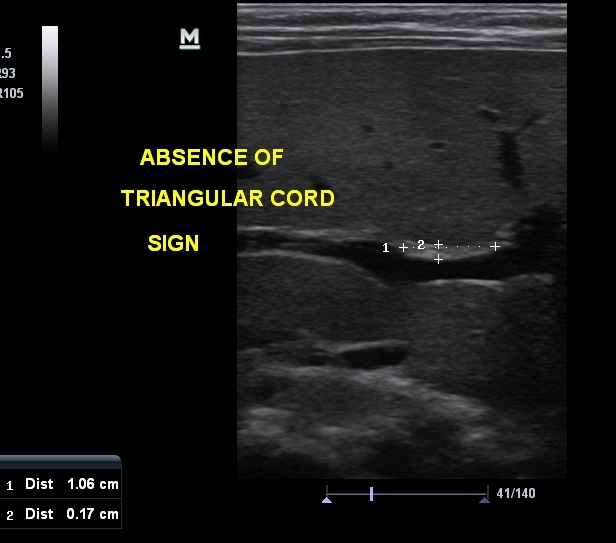

Absence of triangular cord sign (normal) :

Positive of triangular cord sign = thickness of EARPV > 4 mm on a longitudinal scan

(EARPV - echogenic anterior wall of the right portal vein)

Use of a 4-mm thickness as a criterion for diagnosis of biliary atresia has been reported to have sensitivity of 80% , specificity of 98% , a positive predictive value of 94% , a negative predictive value of 94% , and accuracy of 94% .